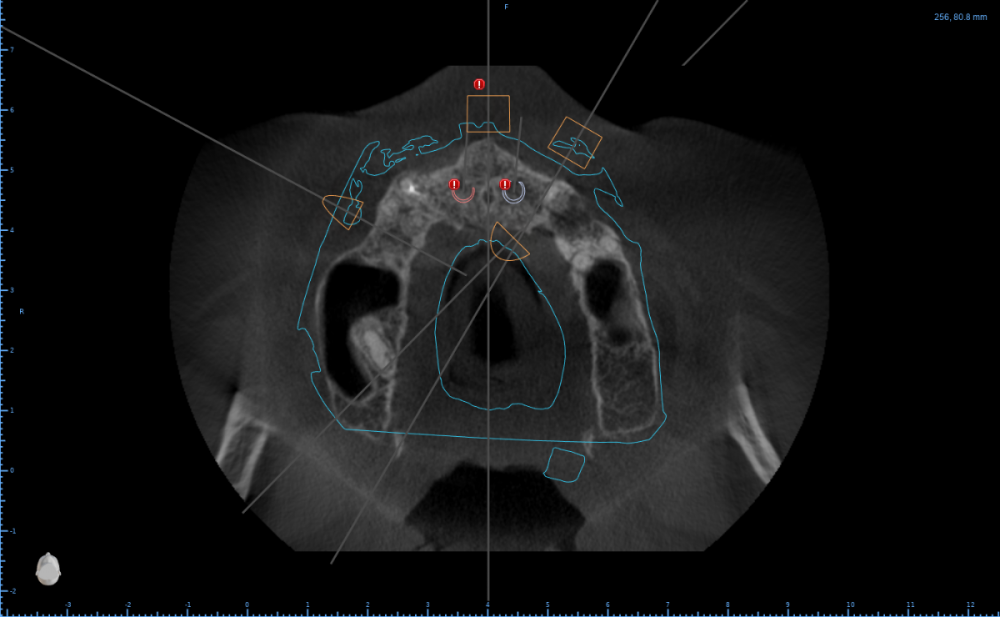

Женька Опубликовано 13 апреля, 2023 Автор Поделиться Опубликовано 13 апреля, 2023 @Irouil если я Вас правильно понял. Ссылка на комментарий

Irouil Опубликовано 13 апреля, 2023 Поделиться Опубликовано 13 апреля, 2023 В общем, я бы поставил во фронт 8-ки по дно носовой полости, боковые классически под углом не обращая внимания на дырку, ориентация сверления боковых лож небно-вестибулярная, чтобы платформа была впритык к небной стенке (даже если будет немного над ней зиять - не страшно), наскреб бы с миру по нитке авто (можно ещё редукцию провести не спиливанием, а сепарированием, тогда полученный блок можно размолоть - графта будет дофига, какой-то фрагмент покрупнее можно использовать каркасно, вклинив его между краями дефекта и мультом), плотно утрамбовал бы вокруг импланта в дефект, с неба vip-ct вокруг мульта по принципу пончо, плотно авто под лоскут Если пару винтов взять для фиксации фрагментов и их вкрутить в стенки дефекта вестибулярно от импланта, то получится вообще отличное место для вклинивания фрагмента Ссылка на комментарий

Женька Опубликовано 13 апреля, 2023 Автор Поделиться Опубликовано 13 апреля, 2023 @Irouil немного не улавливаю, зачем редукция? ведь боковые имплантаты всё-равно на том же уровне что были останутся (то есть ниже фронтальных). Их поднять особо некуда) там и так чуть ли не kissing implants получается... Ссылка на комментарий

Irouil Опубликовано 13 апреля, 2023 Поделиться Опубликовано 13 апреля, 2023 @Женька почему некуда? Попробуйте расставить винты по этой схеме (фронтальные можно немного ангулировать медиально, кстати, чтобы увести их подальше от боковых), что я описал выше. Идея выставлять импланты на разные уровни мне принципиально не нравится Ссылка на комментарий